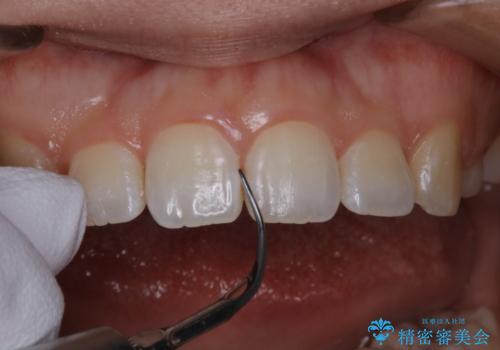

invisalignでの矯正治療が終了した方のPMTC

- 当院でのインビザライン矯正治療が終了し、メンテナンスにいらしている方です。PMTC30分コースを行いました。